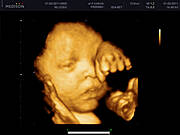

Jessu jakie piękne Irenko. :):):) Za moich czasów nie było kolorowego Usg az się wzruszyłam.

Moi kochani właśnie trwa 35tydzień,maleńki waży 2500kg a ja o 18kg więcej niż parę miesięcy temu,ale co mi tam jak teraz tak bardzo kochamy jeść:)najważniejsze że synek rośnie zdrowo! nie mogę się już doczekać aż wkleję tu jego foto w realu a puki co muszę wam pochwalić się jak maleńki cycka paluszka w brzuszku:D